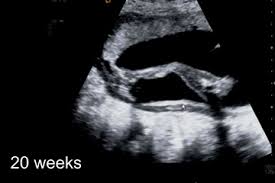

Just like with every human being there might be days when your baby moves a lot in the womb and there might be days when your baby doesnt move a lot in the womb too. If you think that the movement is excessive there tends to be more movement in arms andor legs or if the movement is rhythmic this might be a.

Life can be tough for your little one after exiting the womb. Which explains why the baby moves around a lot during sleeping. Find answers help on ASKPaediatrician why my baby moves a lot while sleeping at FirstCry Parenting. Thats because around half of their sleep time is spent in REM rapid eye movement mode that light active sleep during which babies move dream and maybe wake with a whimper. Observe if your baby reacts even if you carry on with your daily activities. Though this does not happen all the time but only at times. 10 Meditating Moms Calm and Zen mommy equals calm and Zen baby the math doesnt lie. 3 Reasons Your Baby Fights Sleep And 5 Solutions That Will HelpAnd Anwers To 2 Month Old Baby Moves A Lot While Sleeping. Even a minor change or unusual activity may raise questions about whether or not everything is okay.